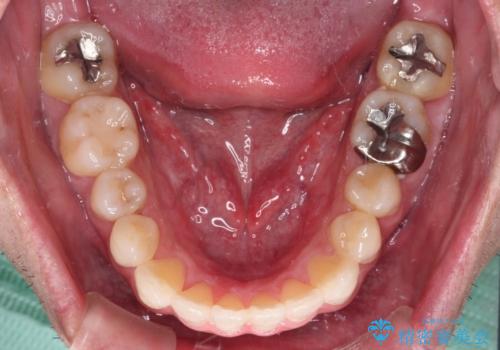

内側に転位した歯とボロボロのむし歯 インビザラインによる矯正治療とむし歯治療

- ボロボロのむし歯とデコボコの歯列を気にして来院された患者様です。

ボロボロとなっていた歯は抜歯が必要な状態でしたが、舌側転位している歯を移動させることで抜歯スペースを埋めることができるため、矯正治療により歯列を整えることとしました。

矯正治療開始時に、インビザライン矯正の加速装置を購入されましたが、インビザライン自体をあまりしっかりと使用できず、4年間の治療期間となりました。